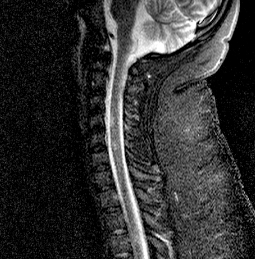

sagT2spine

What type of study is this? Be as specific as possible. How would you describe the abnormal findings?